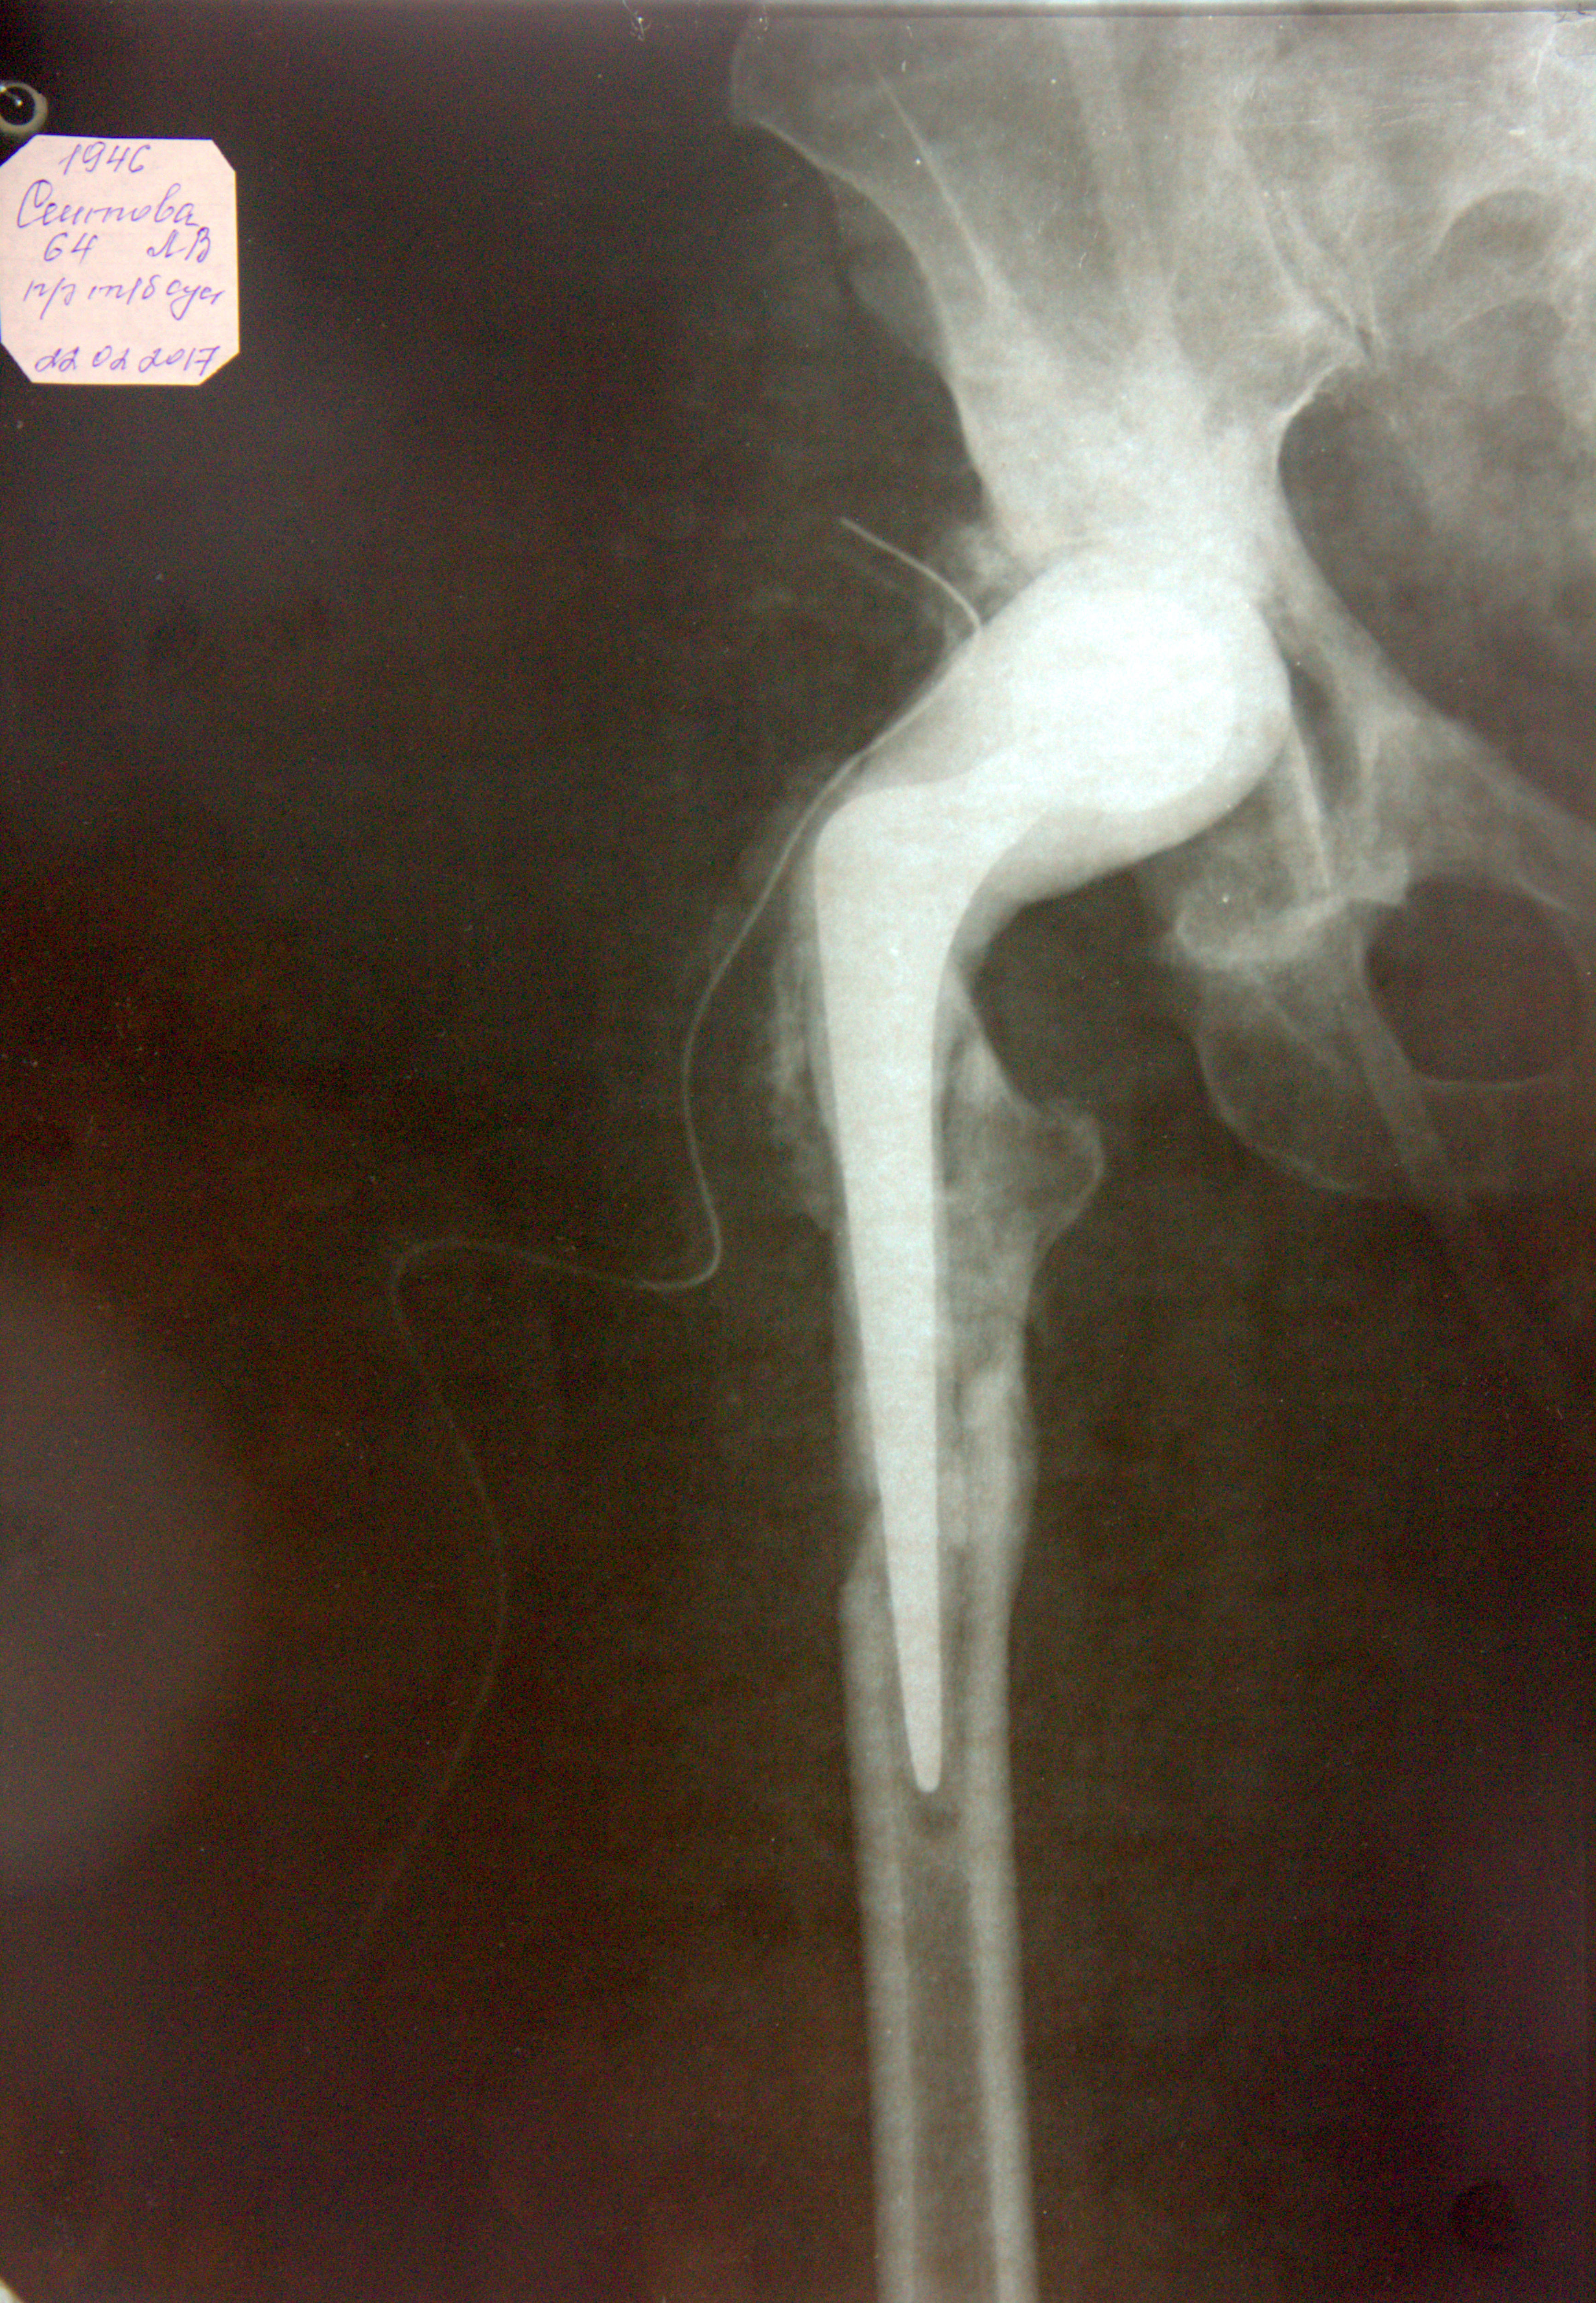

Добрый день! Мне было выполнено эндопротезирование т\б суставов левого в 2001г и правого в 2003г, ревизия правого т\б сустава в 2009г из-за нестабильности чашечки. Все три операции выполнены в ГКБ -13 г. Москва (платно). С 2003г СОЭ повышено 30-54. Два последних года по вечерам субфебрильная температура. 21.02.17г по результатам КТ (признаки остеомиелита справа) в Ярославле была выполнена ревизия правого т\б сустава с удалением компонентов эндопротеза и установкой спейсера с антибиотиком. Спейсер не закреплен из-за слома бедренной кости 8-10см (смотр. на рентгенограмме). В результате любое телодвижение доставляет боль. Уже 1, 5 мес нахожусь в лежачем положении, могу на ходунках пропрыгать на одной ноге м 10. В Архангельске таких операций не делают, сказали, что могут мне операцию сделать только несколько человек в РФ в специализированных центрах и посоветовали обратится в клинику им Вредена Р.Р. в Санкт Петербург. В квотном отделе сказали,что очередь на квоту 3 года, а операцию надо делать через 1, 5 мес. У меня большая просьба к Вам, если у Вас возможность помочь мне сделать операцию в конце мая , июне? С уважением Сеитова Л.В. Письмо пишу повторно, первое отправляла 27 марта, на связи 3 апреля были и звонили Вам с 10 до 11 часов, ответа не было .